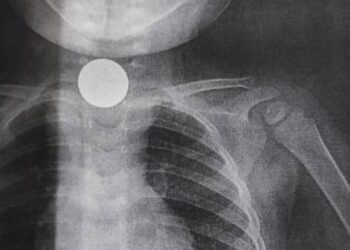

«Жөтөлүп жүрө берген». Ошто 2 жашар наристеге операция жасалды

Ош облустар аралык балдар клиникалык ооруканасы ата-энелерге дайыма балдарды жакшы кароону, алардын коопсуздугун, тазалыгын сактоону суранып, дагы бир жолу кайрылды. Кечээ, 8-сентябрда ооруканада бөтөн затты жутуп алган эки жаш эки ...